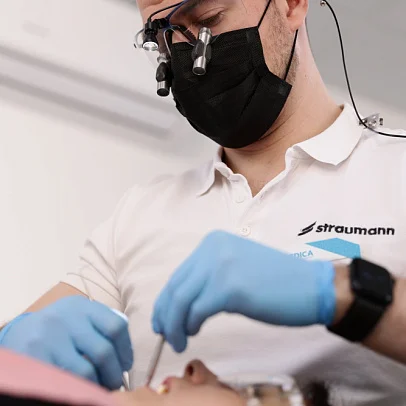

Удобство для врача, комфорт для пациента при установке коронки

Врач использует конструкции, имеющие полированную шейку без заглубления в костную ткань. Это упрощает уход за имплантом в период ожидания его остеоинтеграции. На такой искусственный корень легко устанавливается коронка без необходимости повторного открывания десны.